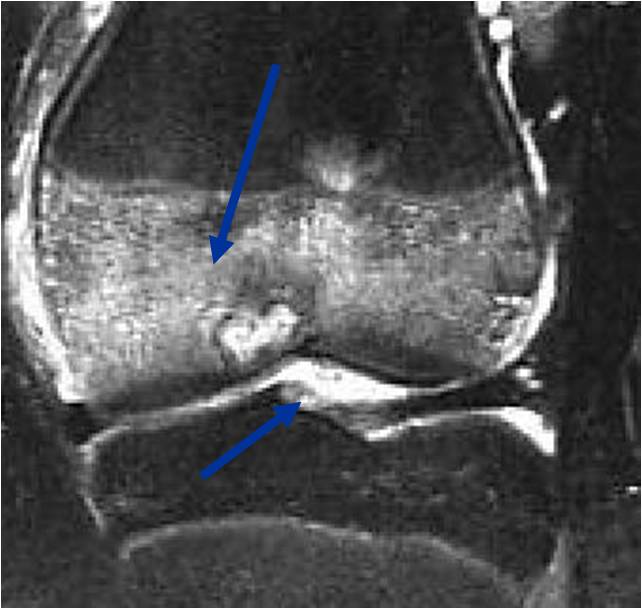

MRI appearance:

- Geographic, well circumscribed lesion in the epiphysis

- Intermediate Signal on T1

- High signal on T2 mixed with low signal areas (low signal areas proposed to be secondary to lysosomal content of highly cellular areas)

- Fluid/Fluid levels demonstrated in tumors that have undergone ABC change (aneurysmal bone cyst change)

- Extensive Surrounding edema is common

- Joint effusion in 30-50% of cases